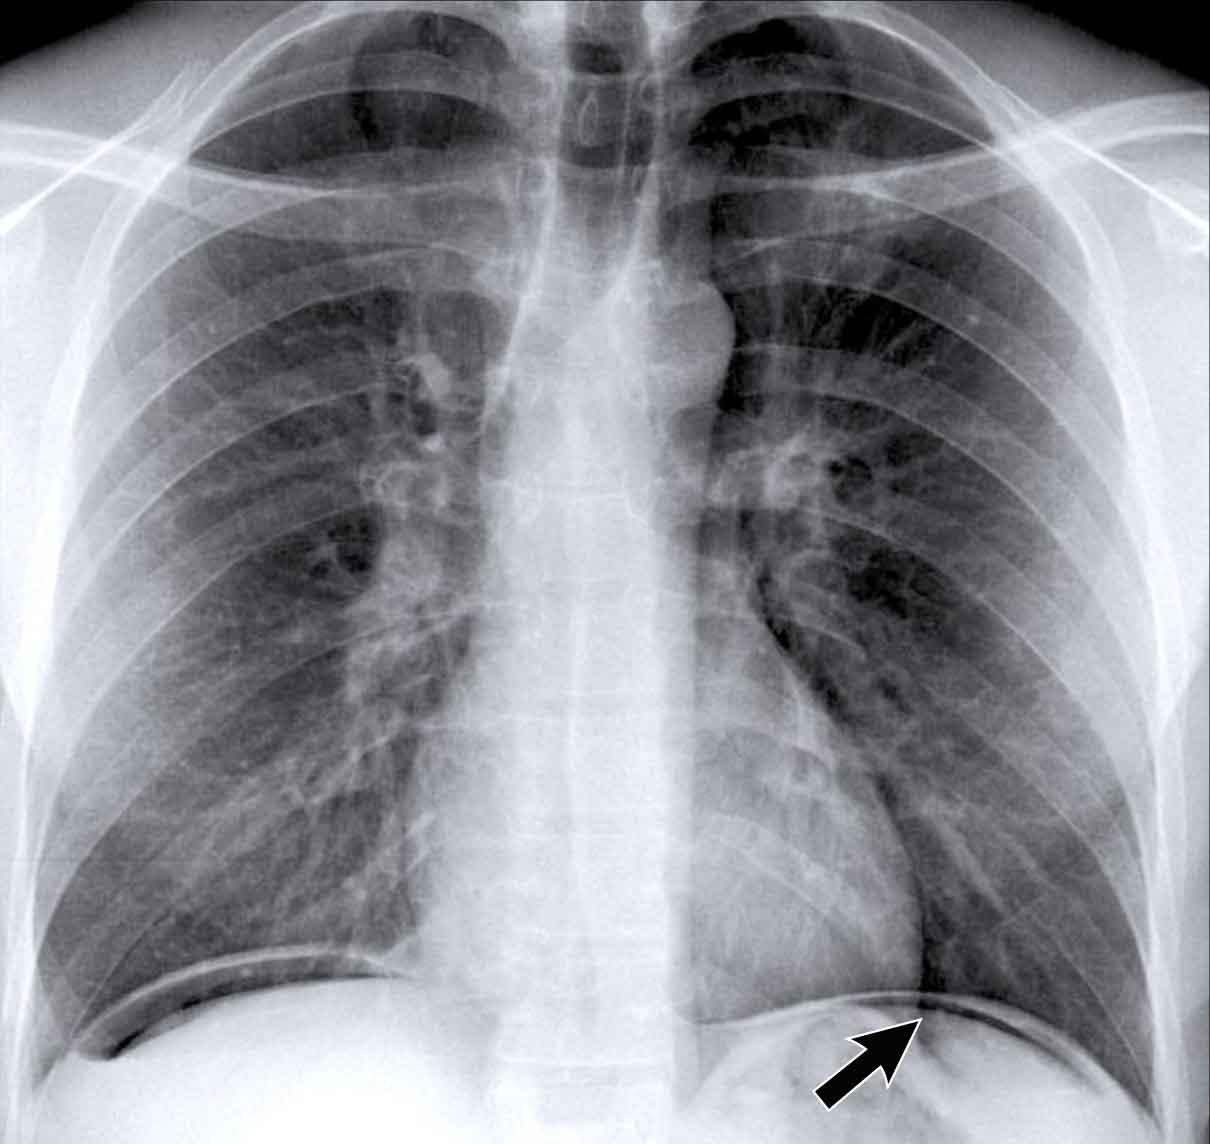

Ca lâm sàng 1: Tư thế PA

- Bờ tim trái bị xóa mờ trên phim X-quang tư thế PA.

- Ngay cả khi chưa xem phim nghiêng, dấu hiệu này đã định khu tổn thương ở phân thùy trước của phổi trái, nhiều khả năng là thùy lưỡi.

- Chẩn đoán: Viêm phổi thùy do Streptococcus pneumoniae.

Ca lâm sàng 2: Tư thế PA

- Quan sát thấy đám đông đặc ở thùy dưới trái (mũi tên vàng).

- Bờ tim trái vẫn được xác định rõ với bóng silhouette bình thường (mũi tên xanh dương), cho thấy tổn thương nằm ở phía sau và không liên quan đến thùy lưỡi.